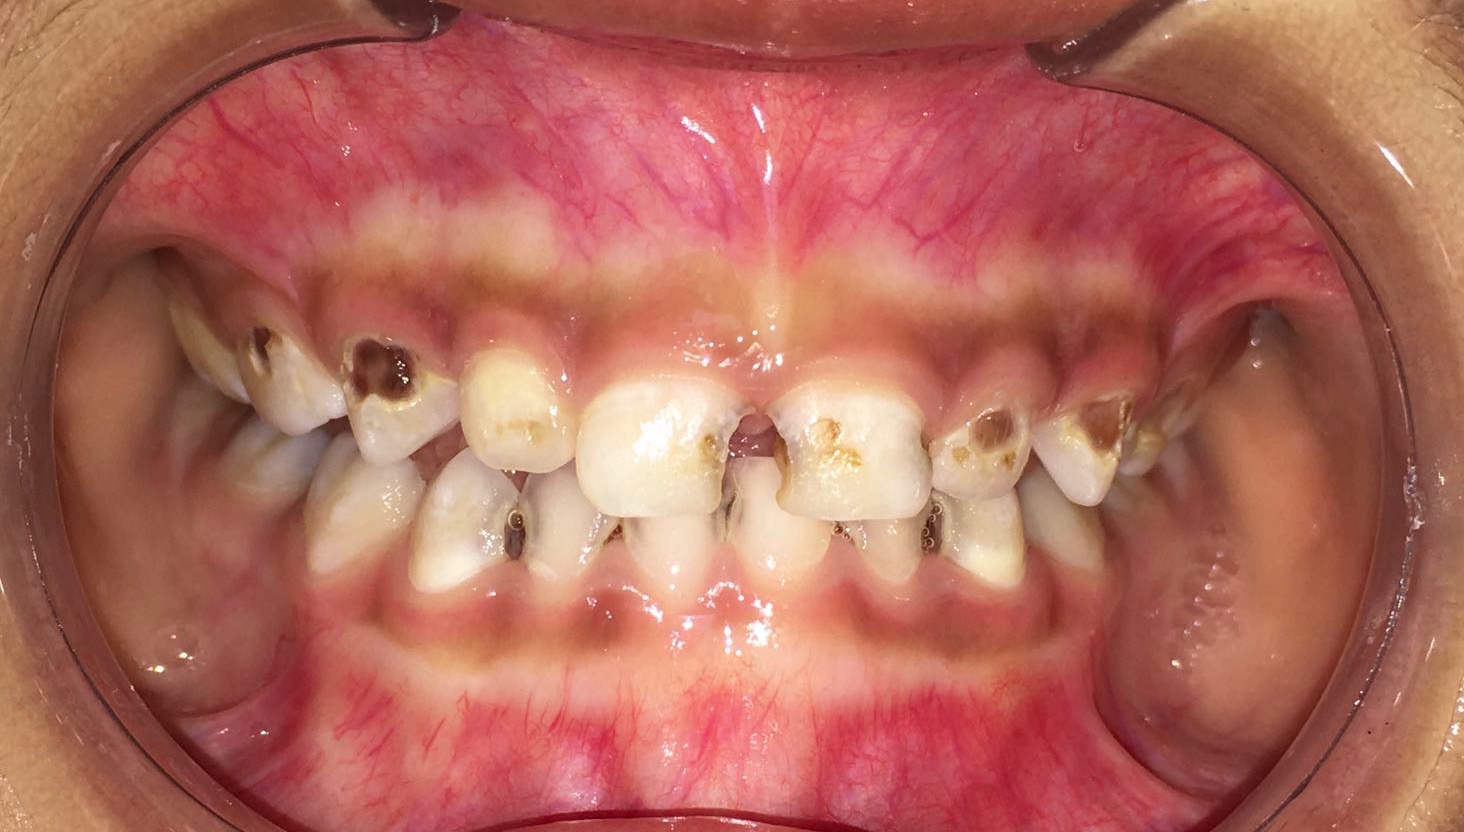

吃糖的最大坏处就是容易导致蛀牙,糖摄入过多,加上不注意口腔卫生致使食物残渣残留,糖会被细菌分解发酵,产生酸性物质,侵蚀牙齿,使牙齿遭到破坏。预防宝宝蛀牙,糖是头号大敌。

致病的糖,不止指名称上带“糖”字的食物,更多的是隐身于各种食物中,尤其是深受宝宝们喜爱的各种零食,如巧克力、冰淇淋、饼干、蛋糕等等。让宝宝少吃甜食和膨化食品,小心食物中的“隐形糖”,不能让孩子养成把饭含在口中、边吃饭边玩的习惯,因为米饭中同样含有糖分。